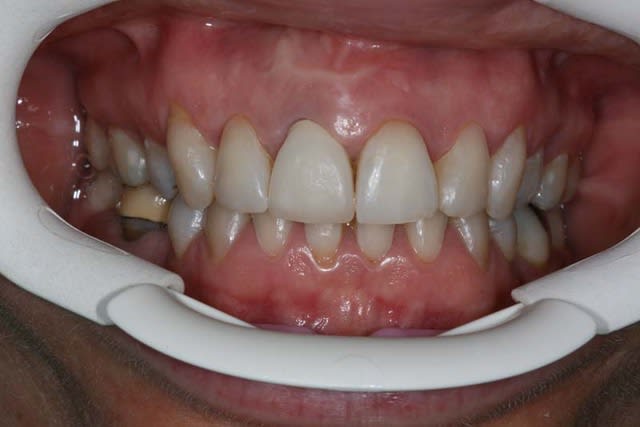

pour ton cas,si tu veux une contention qui te permette de respecter au mieux hygiene,esthetique et fonction dans un avenir durable,je ne vois que 4 ceram,12-11,21-22

une solution combinee et acceptable serait facettes sur 12 et 22(probleme du retour palatin?),puis empreinte envoyee au labo odf qui te modelera un fil tresse colle en palatin de 12 a 22 tout en respectant l'occlusion

au niveau hygiene,ca passe,esthetique et fonction respectees sans trop de sacrifice tissulaire,contention fiable

ben justement je m'étais posé la question si des coiffes ou des facettes solidarisées de 12 à 22 étaient une contention suffisante, étant donné que 12 et 22 risquent de se transformer en facettes et que la patiente n'aime pas la forme de ses 11 et 21.

des avis?